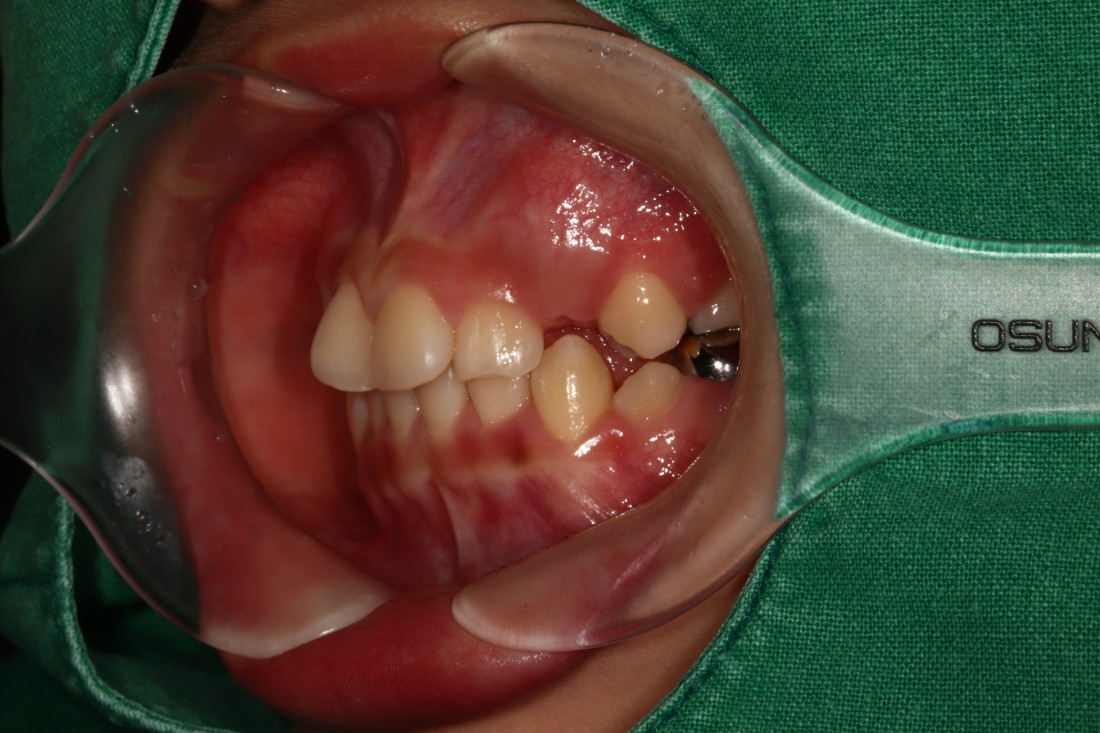

광주 덧니교정 치과에서는

덧니교정 시에

발치를 하는 경우도 있고,

비발치로 진행하는 경우도 있습니다.

치료계획은 모두 경험이 풍부한

교정전문의 대표원장님과

교정 전 정밀검사 결과를 토대로

오랜시간 세심한 상담 후에

결정하고 있습니다.

교정전문의가 봤을 때

발치가 꼭 필요한 경우가 있기 때문에

다양한 덧니교정 케이스와 비교하며

나만을 위한 치료계획을 세우고 있습니다.